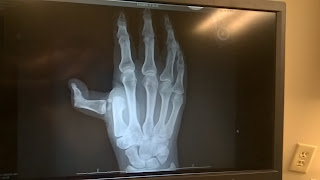

About 2 weeks ago I decided to high five the ice and dislocated my thumb. I am still cooking/baking but taking things a lot slower. Please forgive me for the lack of posts....hopefully I will be back soon.

X-ray from Urgent Care

"That's an odd angle!"